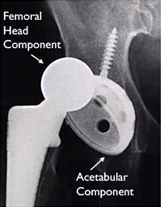

Implant Components

Many different types of designs and materials are currently used in artificial hip joints. All of them consist of two basic components: the ball component (made of highly polished strong metal or ceramic material) and the socket component (a durable cup of plastic, ceramic or metal, which may have an outer metal shell).

The prosthetic components may be "press fit" into the bone to allow your bone to grow onto the components or they may be cemented into place. The decision to press fit or to cement the components is based on a number of factors, such as the quality and strength of your bone. A combination of a cemented stem and a non-cemented socket may also be used.

Your orthopaedic surgeon will choose the type of prosthesis that best meets your needs.